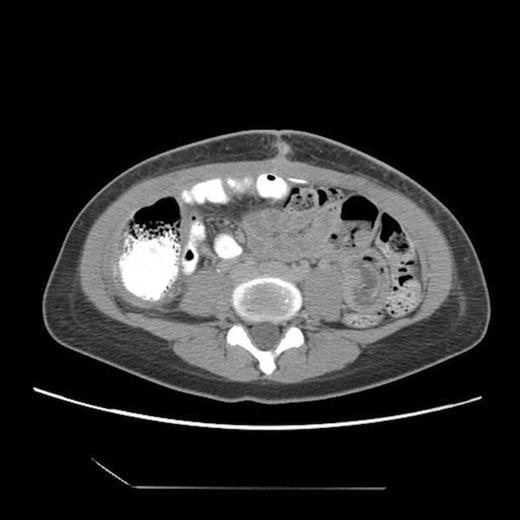

Post-operative abdominal CT demonstrating complete resolution of the fluid compartment

The patient underwent laparoscopic cyst drainage with removal of the cyst wall. A total of 12.7L of fluid was drained. Culture results and routine labs were all negative. A post-operative CT demonstrated complete resolution of the fluid compartment (Fig. 4). The VP shunt catheter was initially left in the abdominal cavity. One month later, however, she developed significant recurrence of fluid collection (Fig. 5) and lethargy from malfunction of the VP shunt. The recurrent fluid was drained under ultrasound guidance, and her abdominal shunt catheter was removed. A new shunt catheter was placed in the right atrium, and the patient made a full recovery without any further complications.